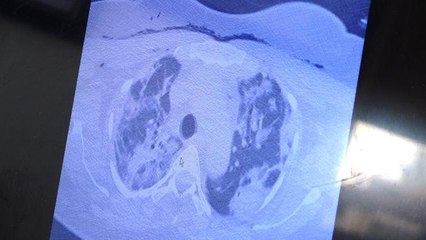

Göğüs Hastalıkları Uzm. Prof. Dr. Şevket Özkaya, "Maalesef virüs artık hasta seçmeye başladı. Akıllı bir organizma gibi davranıyor. Özellikle aşı olmayan grupta tedaviye yanıt vermeyen çok hızlı kötüleşen ve kaybettiğimiz bir hasta grubu ile karşı karşıyayız" dedi.